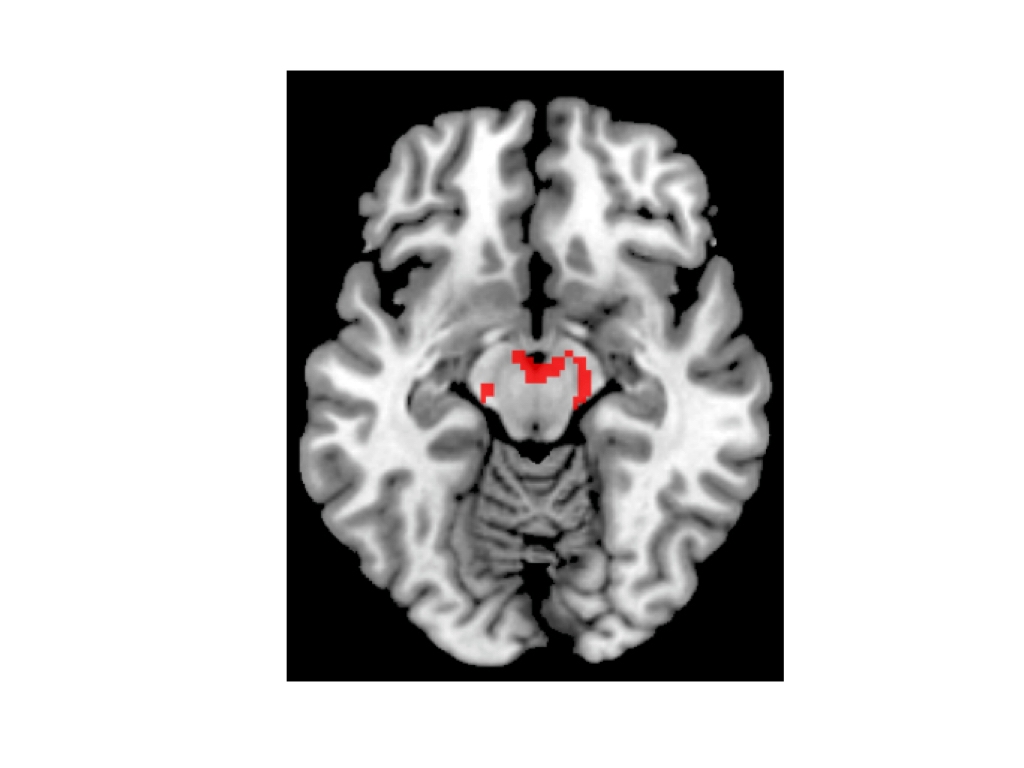

Ma è possibile esporre persone sole a immagini di persone amichevoli che offrono spunti sociali, come un sorriso, e quindi monitorare e registrare i cambiamenti nel flusso sanguigno in diverse parti del cervello utilizzando l’imaging fMRI. E, grazie a precedenti esperimenti, gli scienziati hanno una buona idea di dove cercare nel cervello, un’area analoga a quella che Matthews e Tye hanno studiato sui topi.

Alla fine di ogni sessione, ai soggetti è stato chiesto di salire sullo scanner fMRI e sono stati esposti a immagini diverse: alcune mostravano persone che offrivano segnali sociali non verbali e altre contenevano immagini di cibo. A differenza di Tye e Matthews, Tomova non è stata in grado di individuare i singoli neuroni, ma è stata in grado di monitorare i cambiamenti nel flusso sanguigno all’interno di aree più ampie della scansione, note come voxel, che mostrano l’attività mutevole di popolazioni discrete di diverse migliaia di neuroni. Tomova si è concentrata su aree del mesencefalo note per essere ricche di neuroni associati alla produzione e all’elaborazione del neurotrasmettitore dopamina.

Queste aree sono già state collegate in altri esperimenti alla sensazione di “desiderare” qualcosa. In genere si illuminano in risposta alle immagini del cibo quando una persona ha fame, o a immagini legate alla droga nelle persone con dipendenza. Si è verificato lo stesso comportamento in persone sole quando vengono mostrate loro immagini di un sorriso?

La risposta è stata chiara: dopo l’isolamento sociale, le scansioni cerebrali dei soggetti mostravano molta più attività nel mesencefalo quando venivano mostrate le immagini dei segnali considerati sociali. Quando i soggetti erano affamati, ma non avevano passato un periodo in isolamento, mostravano una reazione altrettanto robusta ai segnali alimentari, ma non a quelli sociali. “Che si tratti della spinta al contatto sociale o della spinta ad altre cose come il cibo, il tipo di rappresentazione sembra essere molto simile”, afferma Tomova.